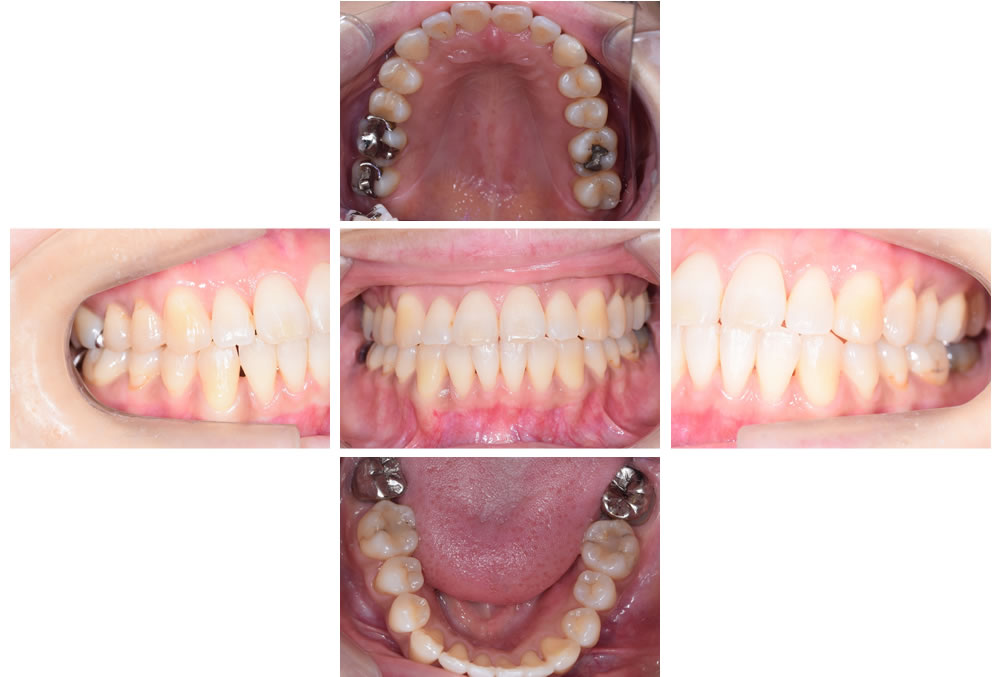

▼頭痛や耳鳴り、目の疲れ、肩や首のコリ、背中の痛み、歯ぎしりなどの症状を訴え、ご来院された患者様。診断、検査の結果、歯並びの不正をはじめ、歯ぎしりや歯の食いしばりによって、様々な不調があらわれている可能性が考えられました。症状の改善、緩和を期待して矯正治療を行いました。

①初診時

| 年齢・性別 | 41歳 女性 |

|---|---|

| 問題点 | 狭窄歯列弓、咬合平面乱れ、下顎の横ズレ |

| 症状 | 頭痛、耳鳴り、目の疲れ、肩、首のコリ 背中の痛み 歯ぎしり |

| 治療説明 | 歯並びの不正と歯ぎしり食いしばりにより、 様々な症状が出ていた患者様 |

| 想定されるリスク | 一般の矯正と同じく、後戻り、歯根吸収、虫歯など |

| 治療期間 | 約30ヶ月 |

| 治療回数 | 約35回 |

| 治療費 | 成人ワイヤー矯正 難症例 93.5万円(税抜85万円/クリーニング代込み) 拡大床 上下 11万円(税抜10万円)×2 リテーナー 上下 2.2万円/(税抜2万円)×2 |

⑧リテーナーによる保定